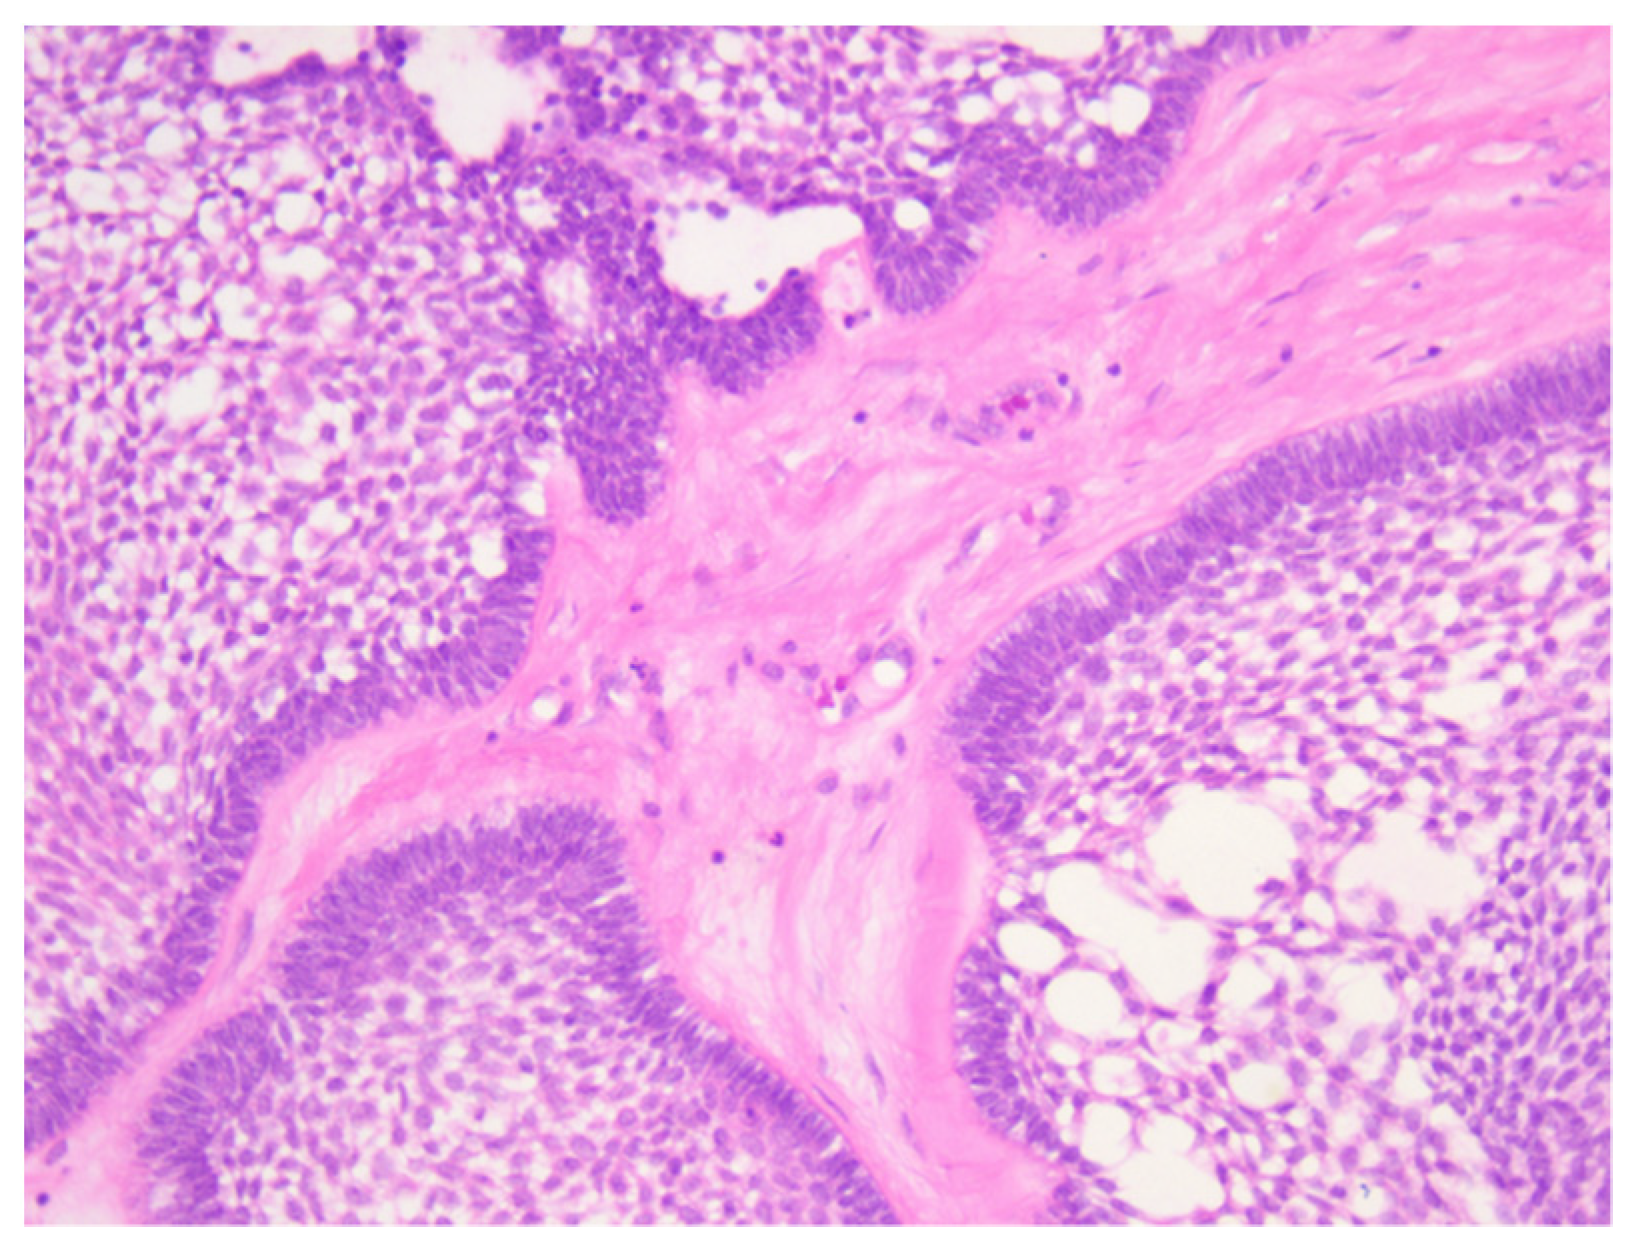

Histopathological examination showed tumor proliferation with a follicular, plexiform and solid (acanthomatous) pattern, with cyst formation. In a follicular pattern, islands of odontogenic epithelium were interspersed within a stoma of mature collagenous connective tissue. The islands had columnar cells at the periphery with reverse polarity and nuclei oriented away from the basal membrane, and the central portion of the islands presented loosely arranged epithelium cells that resemble the stellate reticulum of the developing enamel organ. The plexiform pattern showed an odontogenic epithelium arranged in long cords and stands that surrounded central areas of the supporting stroma. In addition to the interconnecting epithelium stands and cords, islands and sheets of tumors cells were observed. Also, the tumor showed areas of cystic degeneration, with the formation of micro- or macrocysts. Some islands of tumor cells demonstrated central areas of squamous differentiation, with the formation of keratotic pearls or individual keratinizations (Figure 4, Figure 5, Figure 6 and Figure 7). There were no signs of malignant transformation and no immunohistochemical reactions.

Figure 4. Microscopic aspects of ameloblastoma and different growth patterns: (A) solid, (B) plexiform, (C) macrocystic and (D) acanthomatous. HE staining, ob. 10×.

Figure 5. Histopathological aspects of ameloblastoma: (A,B) plexiform pattern, with anastomosing cords and trabeculae of odontogenic epithelial cells scattered in connective loose tissue with inflammatory cells; (C) acanthomatous pattern with squamous metaplasia and unicellular keratinization. HE staining, ob. 10×.

Figure 6. Histopathological aspects of ameloblastoma: (A) acanthomatous pattern with squamous metaplasia and unicellular keratinization; (B) follicular growth pattern, centrally stellate reticulum-like; (C) acanthomatous pattern with squamous metaplasia, stellate cells and microcysts. HE staining, ob. 20×.

Figure 7. Microscopic aspects of ameloblastoma–acanthomatous pattern with squamous metaplasia, stellate cells and microcysts. HE staining, ob. 40×.